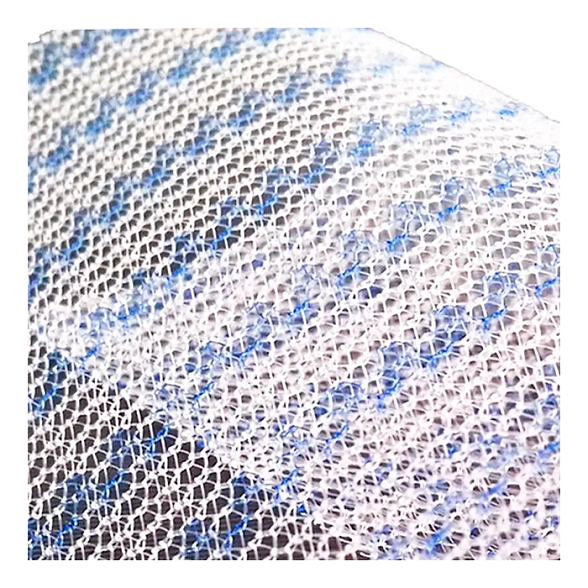

Эндопротез-сетка ЭСФИЛ лёгкий от компании «Линтекс» — это современное и надежное решение для пластики грыж и восстановления мягких тканей в абдоминальной хирургии. Изделие изготовлено из высококачественного монофиламентного полипропилена, что обеспечивает оптимальное сочетание прочности, биологической инертности и удобства для хирурга.

Сетка обладает пониженной плотностью и весом, что минимизирует количество инородного материала в организме пациента, способствуя более комфортному послеоперационному периоду и снижая риск таких осложнений, как хронический болевой синдром и ощущение инородного тела.

- Лёгкость и эластичность: Пониженная поверхностная плотность материала делает сетку более мягкой и податливой. Это упрощает её моделирование и фиксацию в операционной ране, обеспечивая точное анатомическое соответствие.

- Оптимальная интеграция в ткани: Макропористая структура (размер пор более 1 мм) позволяет свободно прорастать соединительной ткани и сосудам через ячейки сетки. Это способствует формированию прочного рубца и снижает риск инкапсуляции, инфекции и серомы.

| Материал | Монофиламентный полипропилен |

| Структура | Макропористая, нерассасывающаяся |

| Цвет | Белый, синий (может варьироваться в зависимости от партии) |